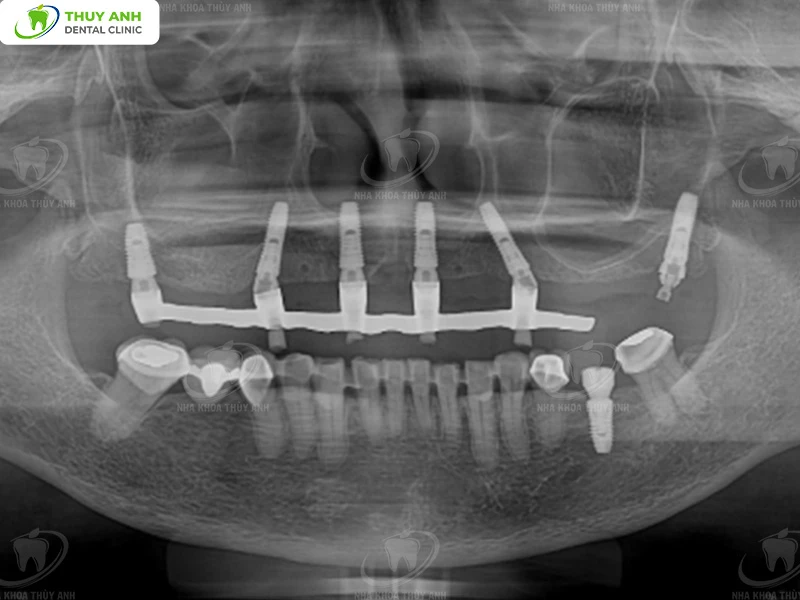

After understanding the patient’s concerns and expectations, a comprehensive diagnostic process was conducted, including:

- Clinical oral examination and assessment of each tooth

- Panoramic X-ray imaging

- Cone Beam CT scan

These data allowed the doctor to accurately evaluate:

- Jawbone volume and density

- Location of critical anatomical structures such as the inferior alveolar nerve, mental nerve, and maxillary sinus

- Condition of remaining teeth

- Degree of occlusal vertical dimension loss due to tooth wear

After collecting complete diagnostic data, all information was transferred into a digital treatment planning system.

Implant Surgery with Surgical Guide

Based on the digital treatment plan, a surgical guide was designed and fabricated.

After thorough discussion, the final treatment plan included:

1. Implant Placement

- 6 implants in the upper jaw: to fully restore missing teeth and create a harmonious aesthetic and functional smile

- 1 implant in the lower jaw